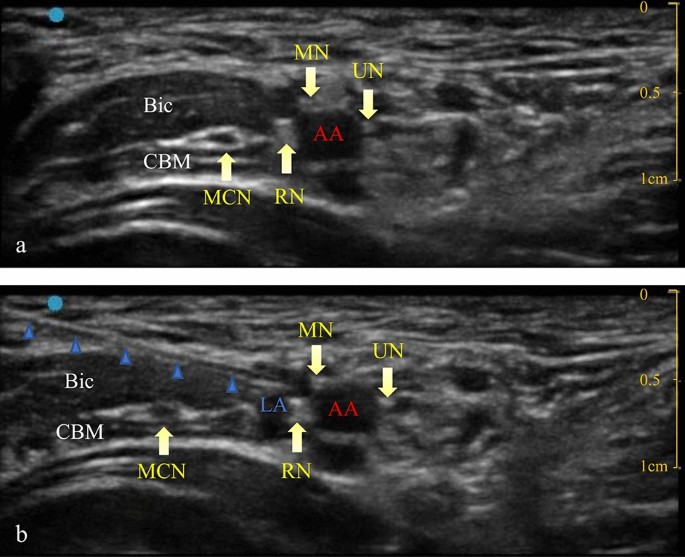

An ultrasound guided ABPB was then performed. The patient was placed in the supine position with the upper limb abducted on the surgical side. The elbow joint was flexed at 90°, exposing the armpit. A bedside ultrasound instrument (Venue 50, GE Medical Systems (China) Co., Ltd) was used with a high-frequency linear array probe (L8-18i, GE Medical Systems (China) Co., Ltd) in nerve block mode. The ultrasound probe was placed in the armpit, and the axillary artery was scanned along its short axis. The axillary artery was centred on the screen, and the locations of the three nerves around the axillary artery were determined. The median nerve is usually located at the 9–12 o’clock position of the axillary artery, the ulnar nerve is usually located at the 2 o’clock position, and the radial nerve is usually located at the 5 o’clock position8. Local anaesthetics were injected near the nerves innervating the skin of the incision. If the surgical area extended beyond the area innervated by a nerve, a single-point injection was still performed, and the anaesthesiologist selected the nerve to be injected. The needle was inserted from the outside of the probe, and the needle tip was placed near the axillary artery and the target nerve. A small amount of saline (not more than 0.5 ml) was injected to ensure that the needle tip was in an ideal position. Next, a set volume of 0.2% ropivacaine was injected. The ultrasound images before and after injection are shown in Fig. 1.